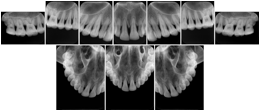

Intra-oral radiography typically involves acquisition of multiple images of various parts of the dentition. Many digital radiographic systems offer customized templates that are used for displaying the images in a study on the screen. These templates may also be referred to as mounts or view sets. The Structured Display Object represents a standard method of encoding and exchanging the layout and intended display of Structured Displays. A structured display object created in this manner could be stored with a study and exchanged with images to allow for complete reproduction of the original exam.

In most standard cases, images are oriented in structured layouts. These structured displays are useful to be shared between providers for reference purposes.

Table OO.1.1-1 shows structured display standard templates, where Viewset ID is based on the Japanese Society for Oral and Maxillofacial Radiology (JSOMR) classification provided by JIRA (Japan Medical Imaging and Radiological Systems Industries Association, www.jira-net.or.jp). Expected or typical teeth to be imaged location, region and designation codes are based on ISO 3950-2010, Dentistry - Designation system for teeth and areas of the oral cavity. For all the hanging protocols listed in OO.1.1-1, the value to use for Hanging Protocol Creator (0072,0008) is "JSOMR" and the value to use for Hanging Protocol Name (0072,0002) does not include "JSOMR" (e.g., "DL-S001A", not "JSOMR DL-S001A").